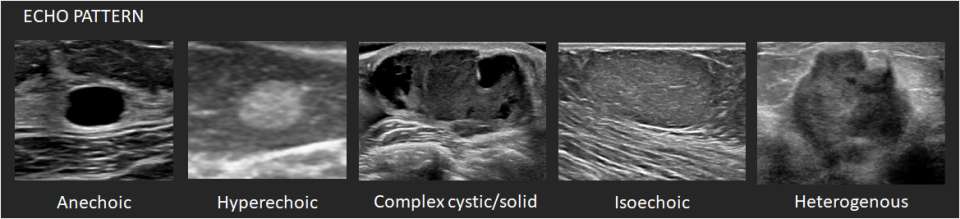

Echo pattern: The echogenicity of masses is described relative to the mammary fat.

1. Anechoic – There are no internal echoes.

2. Hyperechoic – There is increased echogenicity relative to fat or equal to fibroglandular tissue.

3. Complex cystic/solid – There are both anechoic (fluid) and echogenic (solid) components.

4. Hypoechoic – There is decreased echogenicity relative to fat.

5. Isoechoic – There is the same echogenicity as subcutaneous fat.

6. Heterogenous – There is a mixture of echogenic patterns within a solid mass.

Ultrasound Mass Echo Pattern